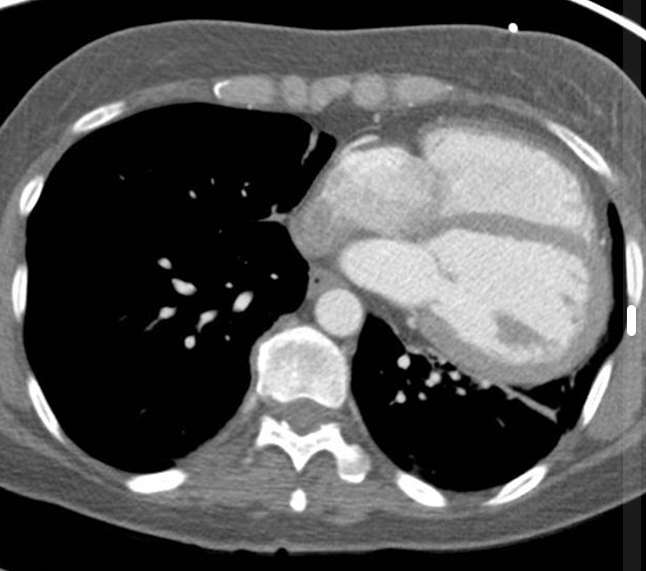

19¼¼ ³²È¯

ƯÀÌ º´·Â ¾øÀ½

¿îµ¿½Ã ÈäºÎ ºÒÆí°¨À» ÁÖ¼Ò·Î ³»¿øÇÔ.